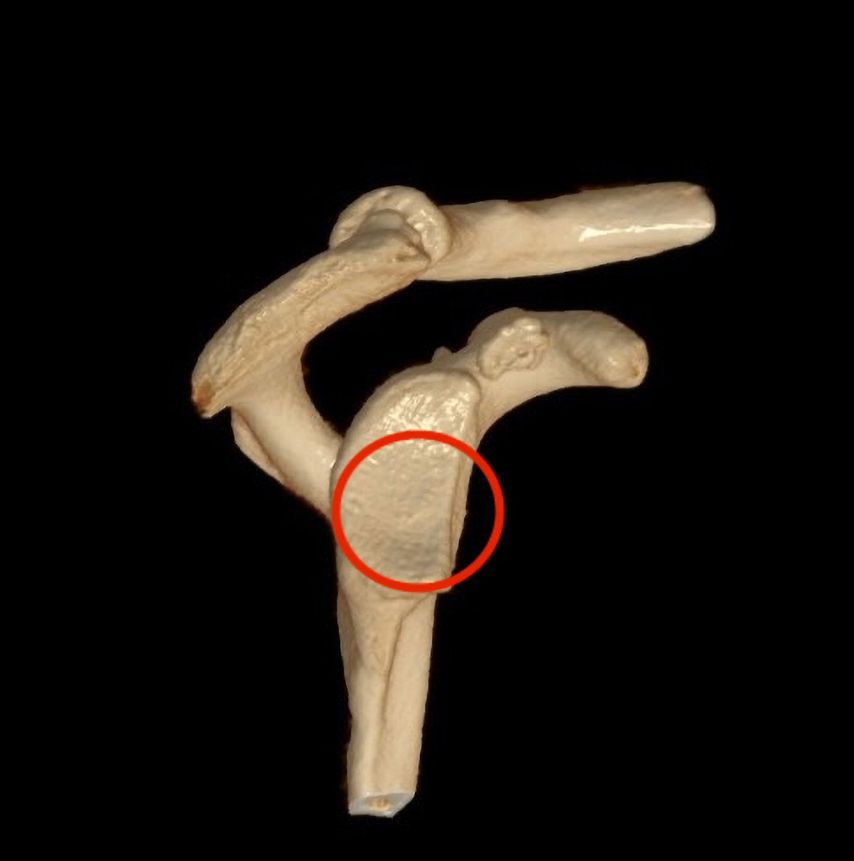

J-Span nach Resch

In unseren Händen hat sich der von Resch schon 1995 beschriebene J-förmige Beckenkammspan zur anatomischen Rekonstruktion bei rezidivierender Schulterluxation bewährt (Abb. 6a–e). Zusätzliche Indikationen sind wie für die Latarjetoperation Pfannendefekte, bipolare Defekte, Patienten nach fehlgeschlagenem arthroskopischem Bankart sowie Patienten mit generalisierter Hyerlaxizität und Patienten, die Kontaktsportarten ausüben. Der Vorteil der J-Span-Plastik liegt in der hohen Plastizität bzw. dem guten Remodelling und in der implantatfreien Verankerung ausschließlich durch Pressfit.89 Abweichend von der klassischen Technik kann der J-Span entweder durch einen reinen Subscapularissplit oder arthroskopisch eingebracht werden, sodass die Vorbehalte bezüglich Schädigung der Subscapularissehne wegfallen.90 Neben einer sehr geringen Rate an Rezidivinstabilitäten und sehr guten klinischen Ergebnissen führt die J-Span-Plastik in hohem Maße zu einer vollen Sportfähigkeit.91,92 Im Verlauf kommt es wie bei jedem Knochenblockverfahren zu einem gewissen Spanremodelling und einer partiellen Resorption, die aber auch im Langzeit-Follow-up zu keiner erhöhten Reluxationshäufigkeit führt.93,94 2,3 Jahre nach der Implantation konnte ein vollständiger Gewebsüberzug über den Span in der MRT festgestellt werden und nach 10,3 Jahren zeigte sich bei einer Reoperation aus anderen Gründen mit Biopsie des Spans ein dem hyalinen Knorpel ähnlicher Überzug.95 In einer prospektiven Studie konnte im Vergleich zur Latarjetoperation kein signifikanter klinischer oder radiologischer Unterschied festgestellt werden. Lediglich die Innenrotation war bei den mit Latarjet versorgten Patienten signifikant geringer.96 Auch Hardware-bedingte Komplikationen kommen beim J-Span im Gegensatz zur Latarjetoperation nicht vor. Erste Ergebnisse mit der arthroskopischen J-Span-Technik zeigen ebenfalls sehr gute klinische und radiologische Ergebnisse. In einer Vergleichsstudie mit der klassischen offenen Technik konnten lediglich eine höhere Spanpositionierung und ein signifikant steilerer Impaktionswinkel festgestellt werden.97,98

Abb. 6a–e: Der J-förmige Beckenkammspan zur anatomischen Rekonstruktion bei rezidivierender Schulterluxation hat sich bewährt